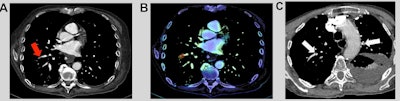

"However, our results were more contrasted for poor-quality examinations and for the appreciation of AI tools by radiologists," the authors wrote. "Indeed, radiologists stressed the importance of AI to strengthen their conclusions, especially to confirm negative findings, or to ensure the absence of distal PE in poor-quality examinations."

In a small cohort of 67 patients with poor-quality exams, the AI algorithm yielded similar accuracy to the radiologists but higher sensitivity and negative predictive value. Although the average interpretation time for CTPA alone increased by one minute and three seconds (7%) after the adoption of AI, 57 (72.2%) of the 79 radiologists who responded to satisfaction surveys deemed the availability of AI to be positive or strongly positive for their diagnostic confidence.